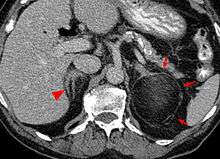

Most myelolipomas are unexpected findings on CT scans and MRI scans of the abdomen. They may sometimes be seen on a plain X-ray films.[6]